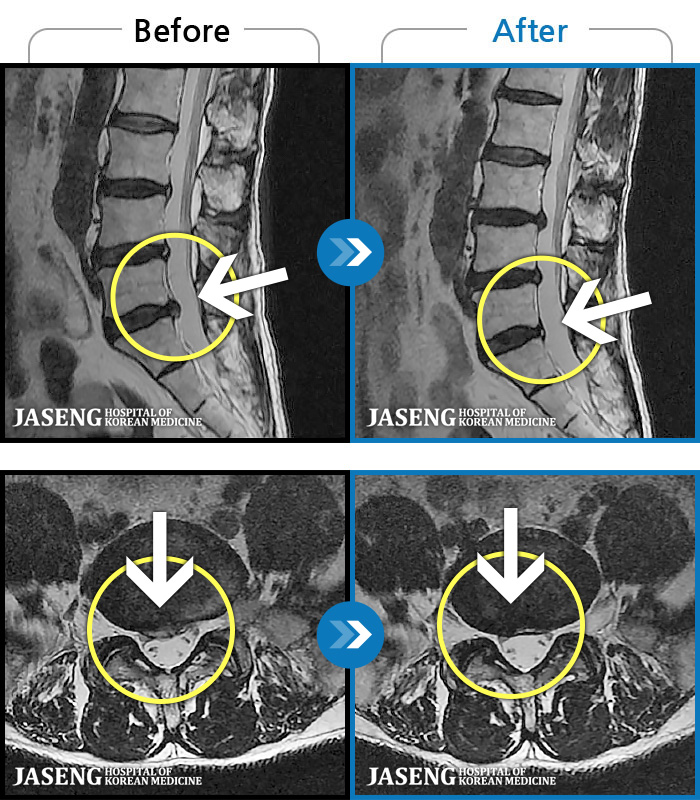

MRI ũ ʸ Ȯϼ.

ȯںп Ǹ ǿ ԿǾ, ο ġ ۿ Ƿ ġḦ Ͻñ ٶϴ.